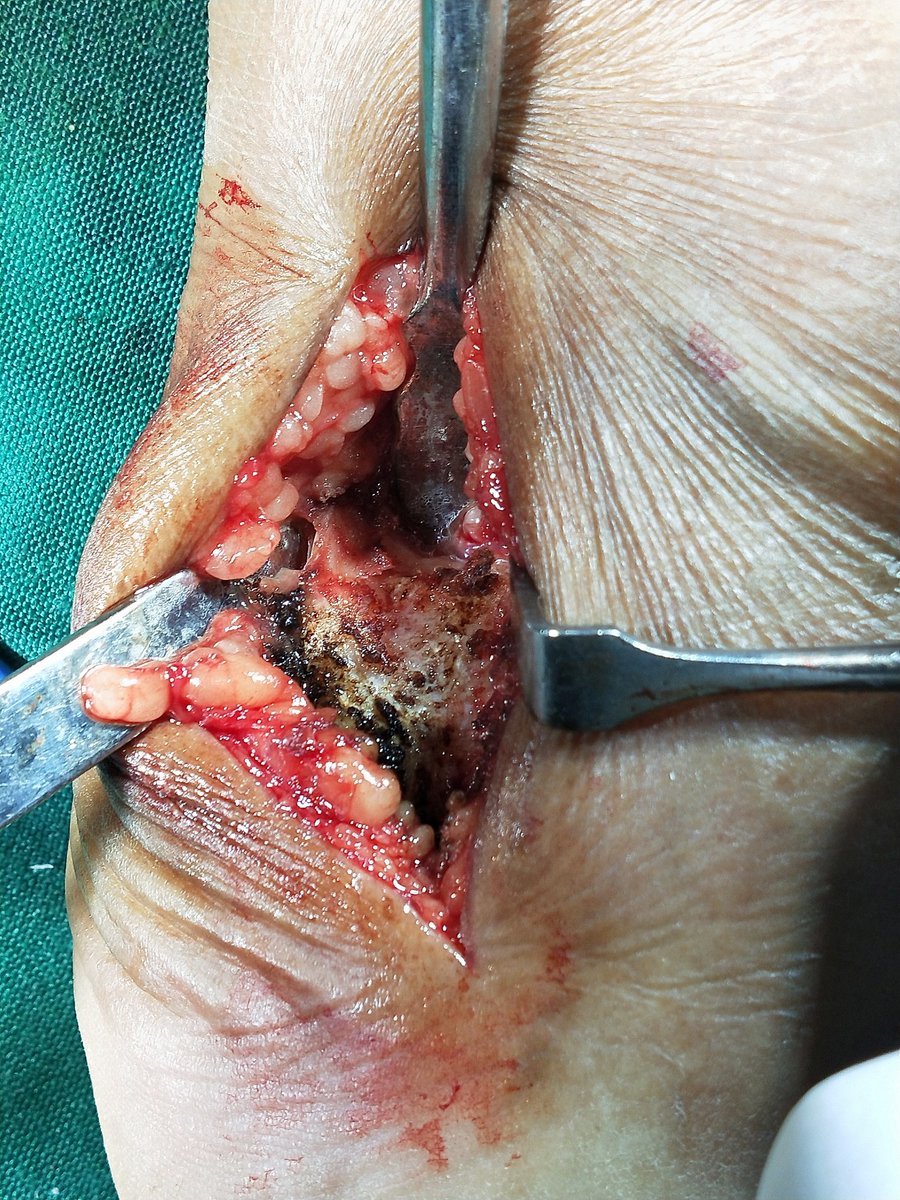

@BostonFootAnkle @DrAdamBitterman @orthoanklefoot This intra-operative shot of the reflected osteotomy makes me briefly freak out every time.

Medial malleolar osteotomies can be useful to access the ankle for severe talus fractures or treatment of large osteochondral lesions of the talus.#orthotwitter 1/x

@FootAndAnkleMD @pratikorho @Footankledc @BostonFootAnkle @TheFootAnkleDoc @NaanDerthaal @natselrox @anilbhatortho @drmaniortho @DrJN_SportsMed I’m definitely interested in those less invasive techniques although I’m not sure how well I could adequately debride the diseased tendon. The postop lateral shows a fair amount of persistent intratendinous calcification.

@pratikorho @Footankledc @BostonFootAnkle @TheFootAnkleDoc @footankle @NaanDerthaal @natselrox @anilbhatortho @drmaniortho @DrJN_SportsMed In the presence of intra-tendinous disease, simple exostectomy is insufficient. Requires Achilles debridement, in this case, complete detachment, and repair. Can be done percutaneously. Endoscopic FHL added here as well (cortical button). Allows early WB and rehab.